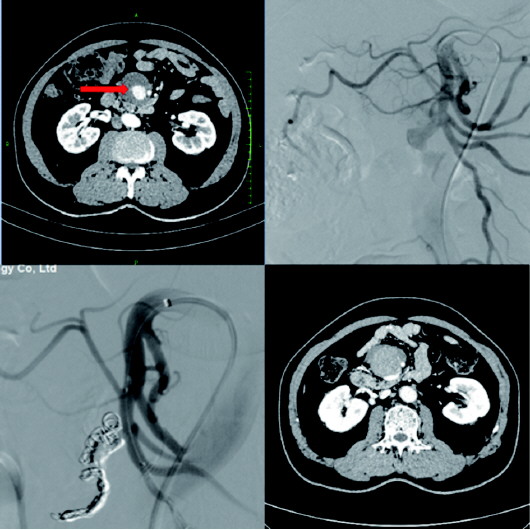

动脉瘤位置深藏于腹腔错综复杂的血管丛中,犹如在迷宫内寻找一个细微的漏点。介入医生需在DSA(数字减影血管造影机)的引导下,将纤细的导管从患者大腿根部的股动脉送入,一路精准“导航”至肠系膜上动脉的靶点位置。整个操作必须在毫米级的血管内完成,对医生的手感、经验和心理素质都是极致考验。肠系膜上动脉是供应大部分小肠和右半结肠的“生命主干道”,绝不能简单“一堵了之”。手术团队必须在不影响肠道正常血供的前提下,精确地栓塞动脉瘤破口。这要求术者具备高超的血管解剖知识和栓塞技术,选择合适的栓塞材料(如弹簧圈、组织胶等),实现“堵漏又保通”的双重目标。

手术过程中,专家们屏息凝神,凭借稳如磐石的双手和鹰一般锐利的眼神,成功超选至责任血管,应用神经介入技术精准释放弹簧圈及注射Onxy胶,瞬间封堵破口。造影显示:动脉瘤瞬间消失,主干血管血流通畅无阻。